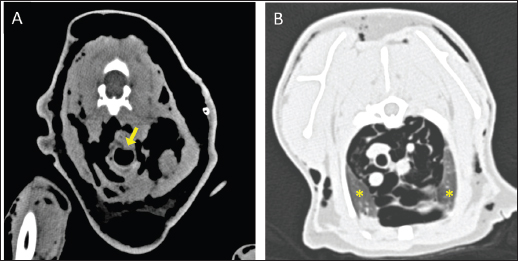

Fig. 2. Transverse CT images acquired with the cat placed in the VetMouse TrapTM. (A) Presence of gas attenuation material in the subcutis around the neck, consistent with subcutaneous emphysema. A dorsal deformation of the cervical trachea with mild reduction of the tracheal diameter is visible in the same scan (A, yellow arrow). (B) The presence of mild pneumo-mediastinum and pneumothorax is further observed, and the collapsed lung lobe is noted (B, yellow asterisk).

On arrival, venous blood gas analysis revealed mild respiratory acidosis and mild hyperlactatemia (Table 1). The complete blood count revealed moderate thrombocytopenia and neutrophilic leukocytosis (Table 2). Biochemical analysis showed elevated liver and muscular enzyme levels and increased serum amyloid A levels (Table 2). Hypofibrinogenemia (1.36 g/l) with unremarkable coagulation time was evident. All abnormalities were consistent with the traumatic event suspected. Thoracic radiographs confirmed the presence of severe subcutaneous emphysema, associated with moderate pneumomediastinum and mild pneumothorax (Fig. 1). Computed tomography (CT) was scheduled for the following day due to the high suspicion of tracheal injury associated with cervical compressive myelopathy. The cat was hospitalized at the intensive care unit under strict monitoring, minimizing manipulation as much as possible. Fluid therapy was set at 2 ml/kg/h IV of lactated Ringer’s solution, together with analgesic therapy with methadone at 0.1 mg/kg IV every 4 hours, and antibiotic therapy with ampicillin-sulbactam 20 mg/kg IV every 8 hours. The cat was mildly symptomatic for the pneumothorax and was therefore managed conservatively. The following day, the clinical parameters were stable, and a progressive reduction of the subcutaneous emphysema and pneumothorax was noted; therefore, the patient was sedated with 0.2 mg/kg of methadone intravenously (IV) and 2 µg/kg of dexmedetomidine IV, and then placed in a VetMouseTrapTM to avoid intubation and general anesthesia. CT scans confirmed the moderate to severe subcutaneous emphysema, pneumomediastinum, and mild pneumothorax (Fig. 2). A dorsal parietal deformation of the cervical trachea of approximately 1 cm in length was observed, causing a mild reduction in the dorsoventral tracheal diameter. There were no other airway injuries. An incomplete fracture line of the caudal margin of the C4 vertebral arch was observed. The fracture line appeared slightly left-lateralized, with a caudal bone fragment approximately 2 mm long and 5 mm wide. This fragment was dislocated into the vertebral canal, narrowing the dorsoventral diameter, with subsequent compression of the spinal cord (Fig. 3). The CT scan confirmed the suspicion of C4 vertebral fracture and tracheal rupture. Endoscopic evaluation of the upper airways and surgical treatment with a dorsal approach for spinal decompression were scheduled for the following day.